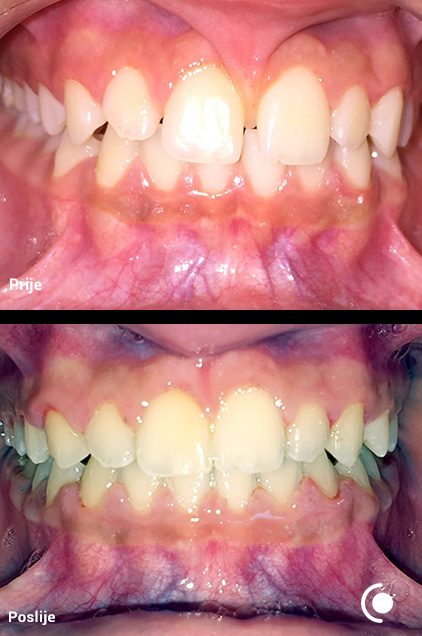

O našoj kvaliteti najbolje govore naši rezultati!